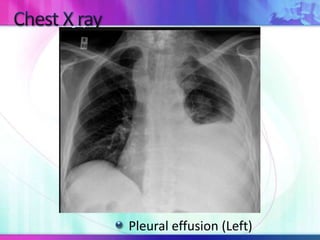

Pleural effusion (Left)

Pleural Effusion Consolidation

Tracheal deviation Contralateral None

Fremitus Decreased Increased

Percussion Dull Dull

Breath sounds Decreased Decreased